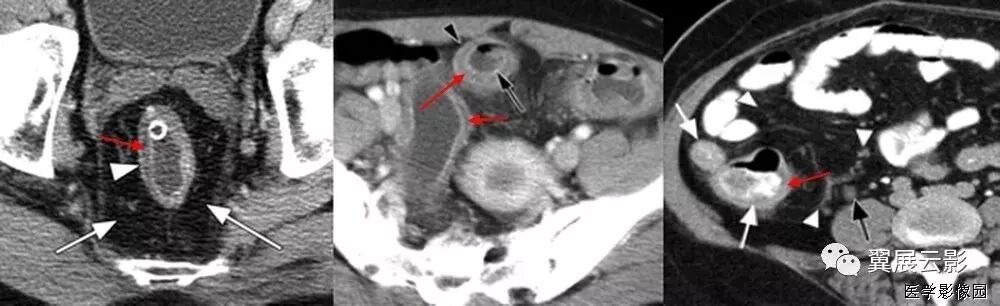

9、高密度环征

高密度环征是指在压痛部位结肠旁可见与结肠壁相连的肿块,近似于乳腺密度,中心密度较低,边缘密度较高,邻近脂肪间隙模糊,局部腹膜增厚。此为炎症导致增厚的脏层腹膜。组织病理显示致病的肠脂垂外脏层腹膜覆盖纤维白细胞渗出物。肠脂垂见于腹水CT。肠脂垂因扭转或自发性静脉血栓而梗死,继发炎症反应,称为原发性肠脂垂炎,区别于因周围器官病变导致的继发肠脂垂炎。

原发性肠脂垂炎的影像表现具有特异性,可以明确诊断。CT显示结肠周围1~4cm的脂肪密度团块周围2~3mm高衰减环。偶尔有高衰减中心,此为栓塞的血管及出血坏死。鉴别诊断包括继发肠脂垂炎和网膜梗死。结肠憩室炎是继发肠脂垂炎最常见的原因,需通过有无临近憩室、结肠壁增厚脓肿除外,多普勒超声有助于炎症和梗死的区别。网膜梗死常更大(3.5~7cm),蛋糕状,预后与原发性肠脂垂炎相。

肠脂垂附于结肠带,特别是沿独立带和网膜带的两侧,多见于盲肠和乙状结肠,为许多大小不等、形状不定的脂肪小突起,它是由肠壁浆膜下的脂肪组织集聚而成。每个肠脂垂通过一个狭窄的短蒂供血,这个带蒂的特点及较大的活动性大大增加了扭转及梗死机率,从而导致局部缺血引起炎症和四周水肿。

由于脂垂分部广泛,患病部位可自盲肠至乙状结肠,疼痛部位亦随之变化,压痛最明显的部位即病变脂垂所在部位,重者可有反跳痛及肌紧张,较少见,不易与急性阑尾炎、乙状结肠憩窒炎及某些妇科疾病相鉴别。当发现阑尾炎症状与体征不相符的患者时,经过CT检查,发现较典型的影像学表现,即可考虑到本病的存在。 因为好发于下腹,临床常诊断结肠憩室炎和阑尾炎原发性肠脂垂炎是自限性疾病,一般1周后自动缓解,因此明确诊断很重要,可以避免不必要的手术和临床处理。

左图:腹部增强CT横扫显示结肠附近高衰减环(箭头)围绕脂肪密度中心。此环为肠脂垂炎症导致外脏层腹膜增厚。

右图:CT显示结肠周围1~4cm的脂肪密度团块周围2~3mm高衰减环。偶尔有高衰减中心,此为栓塞的血管及出血坏死。

结肠旁与结肠壁相连肿块,近似于乳腺密度,中心密度较低,边缘密度较高,邻近脂肪间隙模糊,局部腹膜增厚

10、箭头征

阑尾炎CT的直接征象是阑尾形态的异常, 表现为阑尾外径增粗和阑尾壁的增厚。正常阑尾的直径一般3~5mm,有些报道在阑尾腔内无对比剂的情况下,正常阑尾外径可达11 mm。急性阑尾炎患者的阑尾平均直径达11 mm。不能单凭阑尾增粗(>6 mm)或阑尾壁增厚(>3 mm)来诊断阑尾炎,必须结合其他征象综合考虑。

“箭头”征阑尾炎的一个比较典型的CT表现,是造影剂汇集在盲肠尖端(阑尾起始部)形成的箭头样、鸟嘴样改变,是阑尾炎症蔓延到盲肠尖肠壁的结果。如果在盲肠的尖端汇集的不是高密度的造影剂而是气体,那么显示的就是空箭头征。如果造影剂汇集于结肠憩室的口部,也会显示这样的征象。箭头征也见于急性阑尾炎的CT增强扫描中,急性阑尾炎患者的阑尾血流比率比正常肠道高,增强扫描时可见其强化。部分患者由于炎症时肠壁血管内血栓形成,使局部血流受阻,阑尾血流比率可等于或低于正常肠道,甚至无血流灌注,CT上阑尾表现为等密度,低强化或无强化;另外阑尾炎时,其邻近肠管可继发炎症,局部血流增加,有时CT上可见局部盲肠壁增粗, 强化时增强, 似箭头一样指向病变阑尾。“箭头”征是造影剂汇集在盲肠尖端(阑尾起始部)形成的箭头样、鸟嘴样改变,是阑尾炎症蔓延到盲肠肠壁的结果。见到此征象, 有文献报道,阑尾炎的特异度几达100%。有些患者由于炎症较轻,肠道血流可无明显改变;也有些病例,可能是肠壁部分血流受阻,与炎症引起的血管扩张相抵消。因而其血运明显受阻,局部造影剂减少所致。

阑尾粪石可能增强阑尾穿孔的机会,当发现阑尾钙化或阑尾粪石,同时合并阑尾周围炎时,是诊断阑尾炎的可靠征象。阑尾粪石也可出现在阑尾穿孔形成的脓肿或蜂窝织炎内。

阑尾周围炎表现为阑尾周围脂肪组织中条索状、斑片状密度增高影(称脂肪条带征)、结肠后筋膜增厚、阑尾周围液体渗出,局部形成脓肿。阑尾周围炎只是阑尾炎的一种主要间接征象,不能单凭此诊断阑尾炎。阑尾周围炎性反应或右下腹脓肿提示阑尾炎,但Crohn 病、盲肠炎、憩室炎、肿瘤穿孔和盆腔炎等亦可有相似的表现,应与之鉴别。

通过对阑尾强化程度和阑尾周围炎症改变对急性阑尾炎的严重程度作出初步评估,指导临床治疗。正确选择治疗方法基于对急性阑尾炎的正确诊断及对其严重程度的分级,正确诊断急性阑尾炎并区分卡他性阑尾炎、蜂窝织阑尾炎及坏疽性阑尾炎非常重要。总之,阑尾直径增粗>6 mm,阑尾壁高度强化伴有或不伴有阑尾周围炎症改变或阑尾中、低度强化,可作为诊断阑尾炎的依据;阑尾周围是否出现炎症可作为区分卡他性阑尾炎与其他类型阑尾炎的依据。

阑尾增粗,壁增厚、阑尾腔内可减低密度条带影,为阑尾腔内的液体,阑尾根部与盲肠交界处的官腔内进入造影剂形成边缘不规则的尖角状,即“箭头征”。